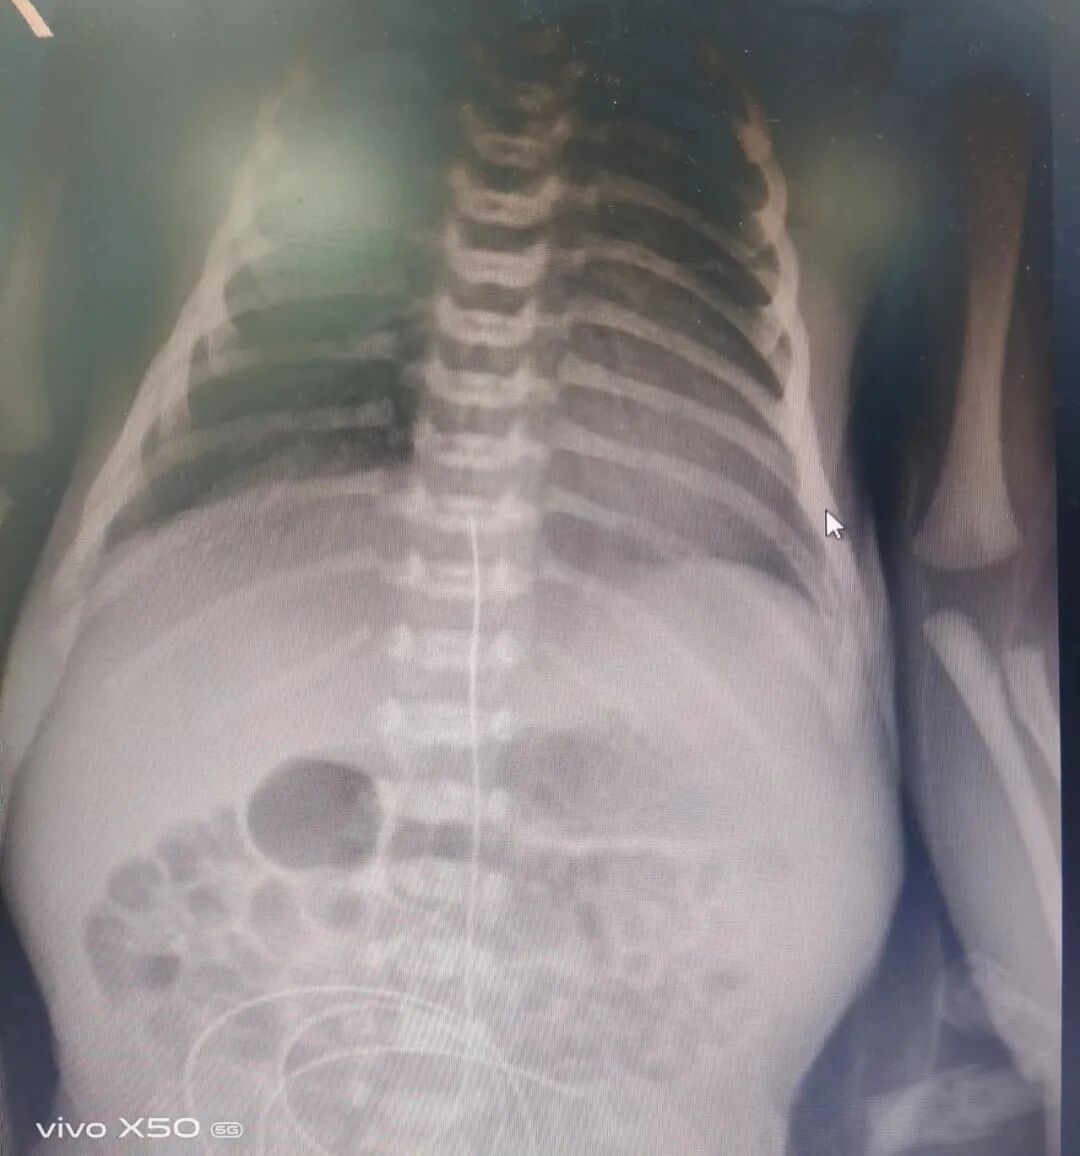

近日,区人民医院儿科(新生儿科)成功为一例重度窒息新生儿实施“脐静脉导管置入术”,为宝宝打通了“生命线”。

近日,恩阳区人民医院儿科(新生儿科)收治了一名重度窒息新生儿,该患儿因出生后室息,导致大脑、胃肠道等脏器缺氧缺血,患儿吃奶反应差,需通过肠外提供葡萄糖、氨基酸、脂质、维生素以及矿物质等营养来满足新生儿生长所需。

为尽快解决患儿体重增长缓慢的问题,医务人员拟为患儿实施“脐静脉导管置入术”为其治疗。当天,在市中心医院帮扶老师的指导下,顺利实施院内首例“脐静脉导管置入术”,置管后,经过规范化治疗和精细化护理,该患儿已于近日顺利康复出院。此项技术的成功开展标志着区人民医院儿科(新生儿科)危重新生儿救治水平再上新台阶。

技术介绍:脐静脉置管(UVC)是新生儿重症监护病房救治危重新生儿的重要技术。主要适用于早产儿(极低和超低出生体重儿)、室息复苏、换血、需要中心静脉、紧急血管通路等。

置管后可以避免长期反复静脉穿刺,从而减轻新生儿的痛苦。脐静脉置管可以进行高渗液体,比如脂肪乳,以及钙剂等的输入,避免血管的刺激而引起静脉炎、血管钙化。脐静脉置管后可以保留两周左右,对于长期住院,尤其是早产儿、低出生体重儿、极低出生体重儿的治疗,是十分有必要的。